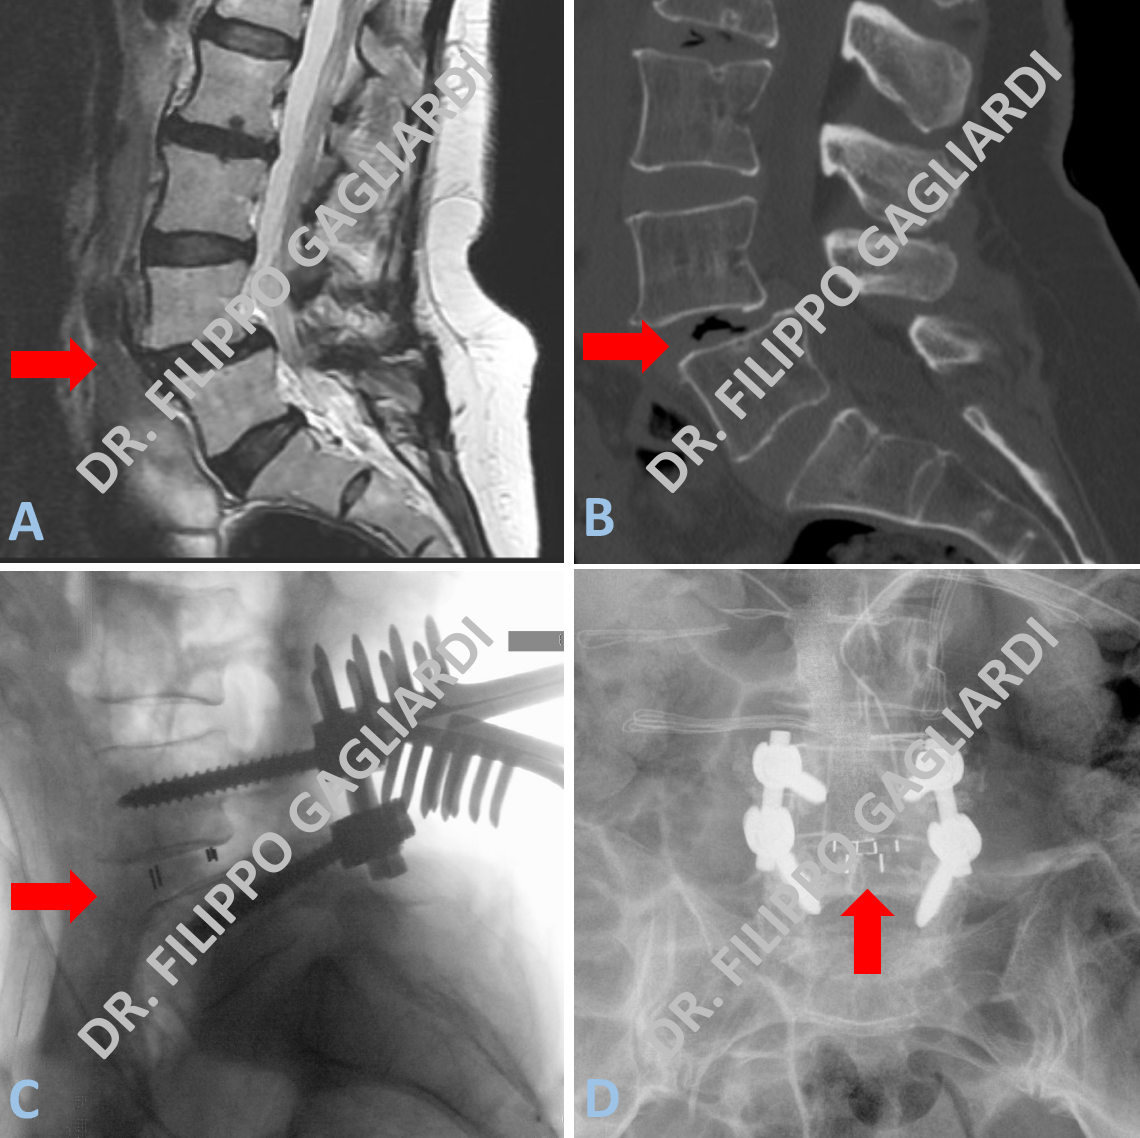

Caso di patologia lombare degenerativa: il Paziente presentava anterolistesi degenerativa (scivolamento anteriore su base artrosica) della quarta vertebra lombare (L4) sulla quinta vertebra lombare (L5) (spondilolistesi). Il Paziente soffriva di lombalgia con irradiazione del dolore ad entrambe gli arti inferiori. In particolare accusava dolore bilateralmente al gluteo, alla faccia laterale della coscia, alla faccia anteriore della gamba fino al dorso del piede. Le Figura A mostra lo studio di RM pre-operatorio che documenta l’anterolistesi associata alla degenerazione del disco intervertebrale L4-L5 che appare schiacciato e disidratato (freccia rossa). Il quadro radiologico è confermato dallo studio TC pre-operatorio. La Figura B, infatti, documenta la presenza di aria (area nera) dentro il disco ovvero una degenerazione gassosa del disco intervertebrale (freccia rossa). Il paziente è stato sottoposto ad un intervento di stabilizzazione vertebrale per via posteriore. Sono state posizionate 4 viti trans-peduncolari a livello di L4 e L5. È stato asportato il disco intervertebrale degenerato e al suo posto sono state posizionate due piccole gabbie in titanio. L’intervento è tecnicamente definito con l’acronimo PLIF (posterior lumbar interbody fusion), ovvero “fusione lombare inter-somatica per via posteriore” con posizionamento di due gabbie di titanio a sostituire il disco intervertebrale malato. La Figura C mostra il controllo radiologico intra-operatorio in proiezione laterale (freccia rossa). La Figura D mostra il controllo radiologico post-operatorio in proiezione antero-posteriore (freccia rossa). Si conferma il corretto posizionamento delle viti e la presenza delle gabbie in titanio dove precedentemente c’era il disco intervertebrale.